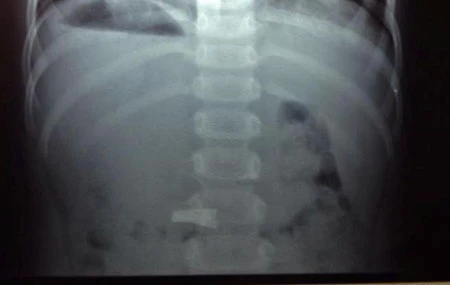

Sau đó cháu Mai Quyên được chuyển đến Khoa ngoại tổng hợp, Bệnh viện nhi Hải Phòng để cấp cứu. Kết quả chụp X.Quang cho thấy chiếc cặp đã nằm ngang yên vị trong dạ dày của bé. Các bác sĩ tại đây đã ưu tiên việc theo dõi để mong muốn chiếc cặp sẽ theo ra bằng đường hậu môn khi bé đi vệ sinh. Sau gần 2 ngày theo dõi, chiếc cặp vẫn không có biểu hiện tự ra như mong muốn, kế hoạch mổ lấy dị vậy cho bé đã được tính tới.

Kết quả chụp  X.Quang cho thấy chiếc cặp yên vị quay ngang trong dạ dày bé